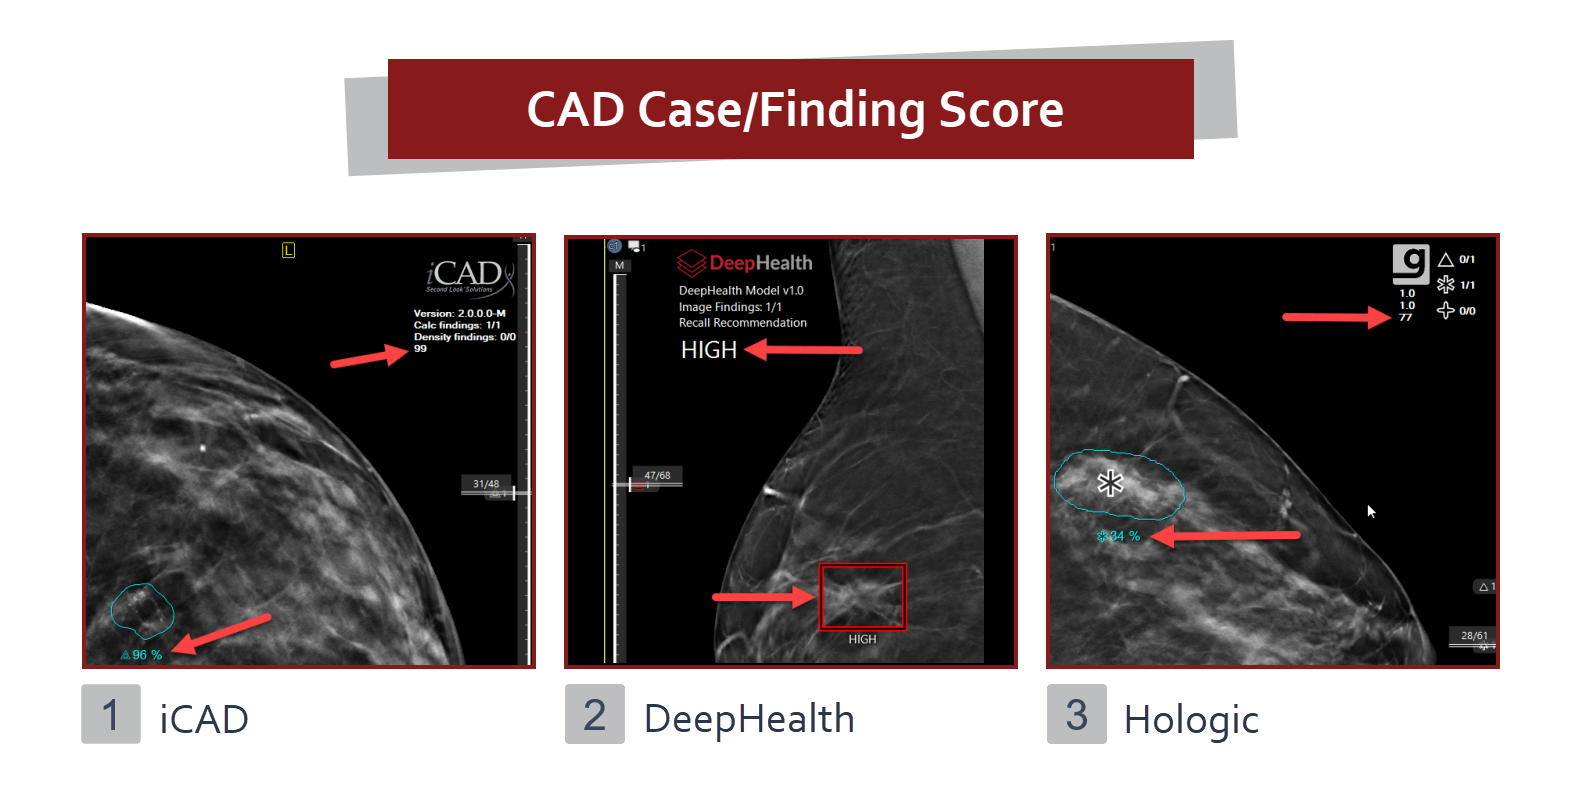

A CAD mutató számítógéppel támogatott diagnózist nyújt a mammográfia képekhez.

Az eRAD PACS érvényesítette a következő CAD rendszerek CAD strukturálású lelet objektumait.

Egyes CAD-gyártók esetpontszámokat és/vagy leleteket adnak. Az eset pontszáma a CAD fejlécben található, és a képen lévő jelölés mellett egy egyedi leletpontszám látható.